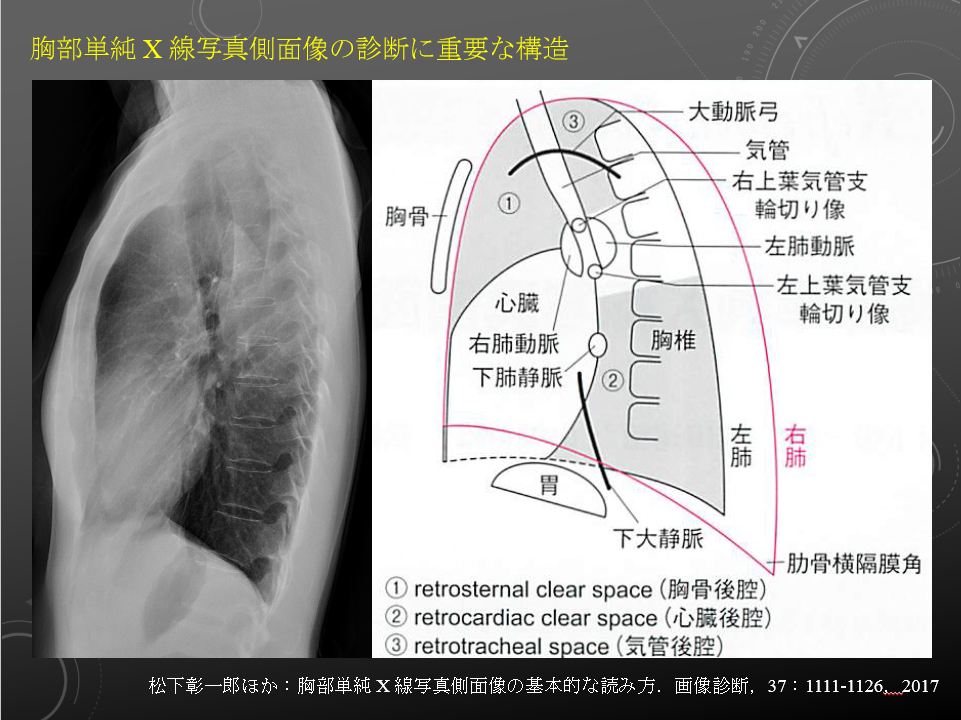

胸部:吸気/呼気、側面

右肺動脈は中間気管支幹の前を横切りながら右下肺野に向かう。

左肺動脈は左主気管支内側を前から後ろに乗りこえ、下方に走行する。

左は右より 1-2cm 高い。

右肺動脈は中間気管支幹の前を横切りながら右下肺野に向かう。

左肺動脈は左主気管支内側を前から後ろに乗りこえ、下方に走行する。

左は右より 1-2cm 高い。

気道の透亮像の濃度は前部(右肺動脈+左右の上肺静脈)が後部(左の肺動脈)よりも高いのが普通である。